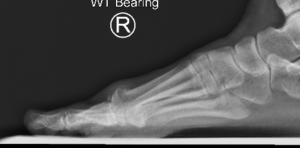

Figure1 and 2: Pre op x-rays showing joint degenerating including joint space narrowing, bone spurs and loose bone fragments.